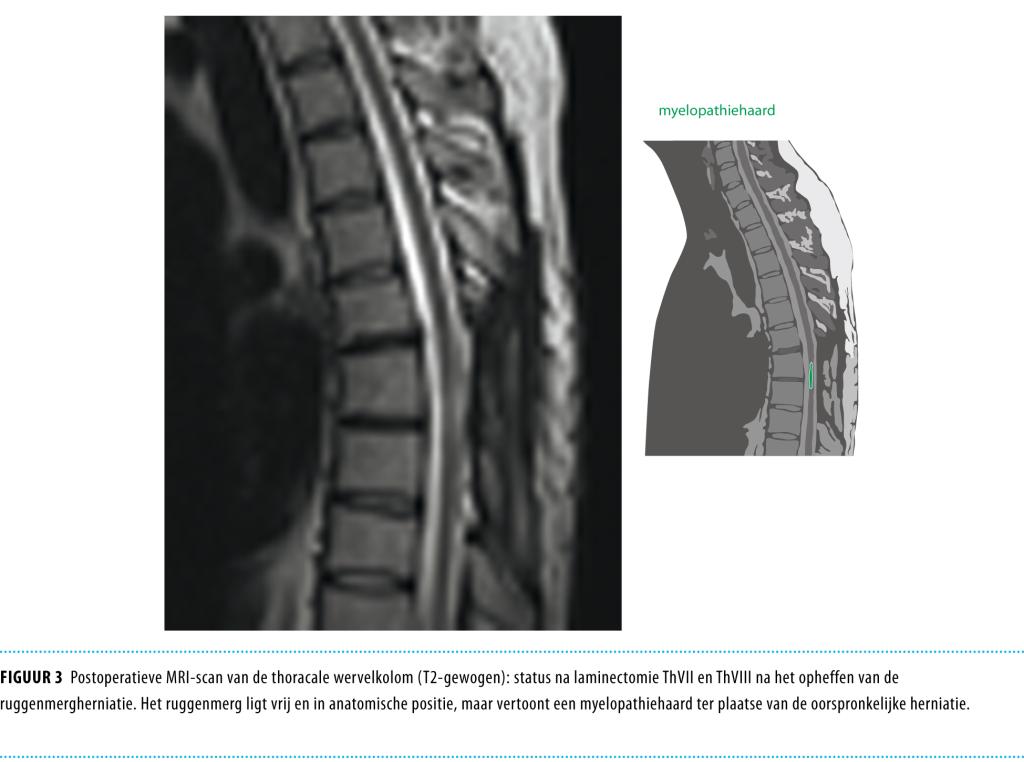

Na een follow-up van 6 maanden waren de erectiestoornissen afgenomen, maar bleven de gevoelsstoornissen onveranderd aanwezig. De MRI-scan die ter controle werd gemaakt, toonde normalisatie van de positie van het ruggenmerg op niveau Thvii-Thviii. In het ruggenmerg was een duidelijke restafwijking in de vorm van een myelopathiehaard zichtbaar in het gedeelte dat oorspronkelijk was gehernieerd (figuur 3).

Figuur 3